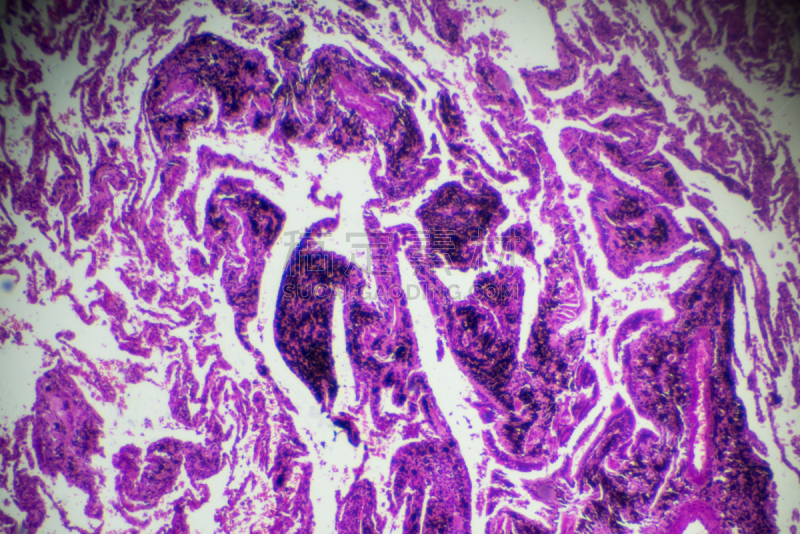

一个人的肝癌详情